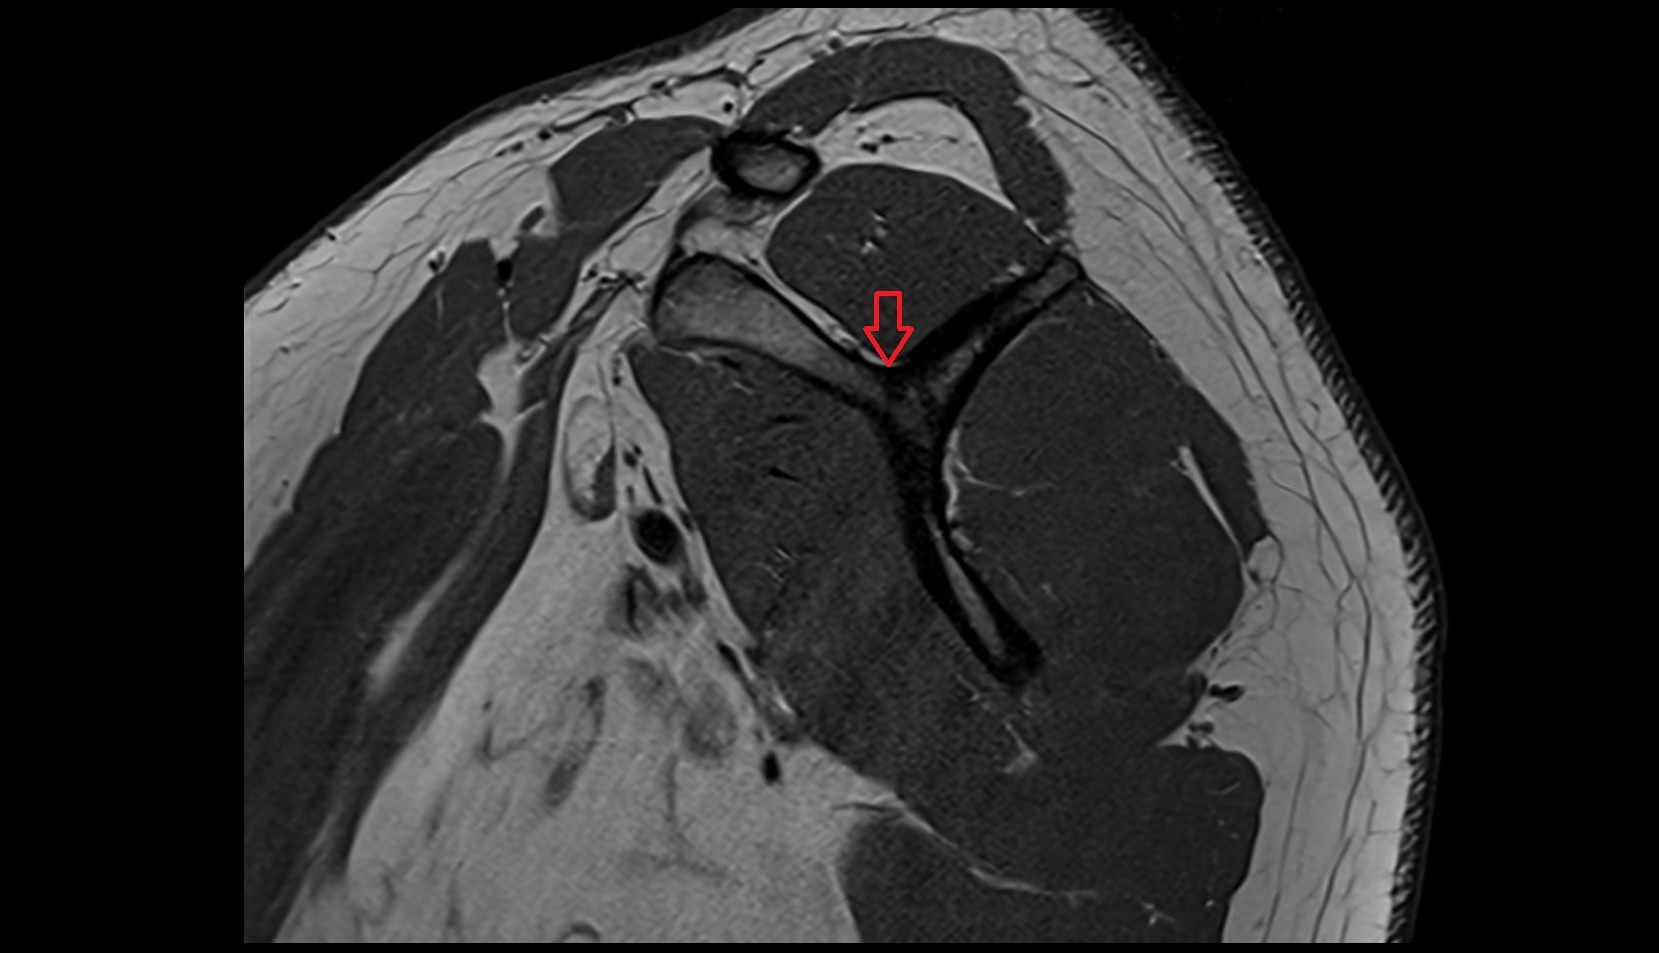

- Temporomandibular joint

- Mandibular condyle

- Mandibular fossa

- Articular disc of temporomandibular joint

- Intermediate zone of articular disc

- Superior retrodiscal layer